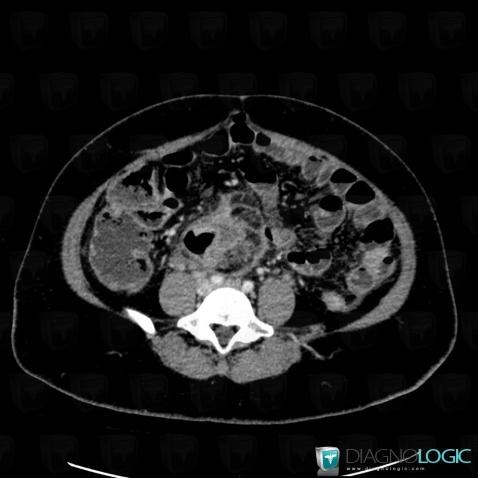

Colon cancer, Colon, CT

Here is the specific information in the key image above:

- Diagnosis Colon cancer, Location(s) Colon, with gamuts Thickening of colon wall, Colonic mass or filling defect

Abscess, Retroperitoneum, CT

- Diagnosis Abscess, Location(s) Retroperitoneum, with gamuts